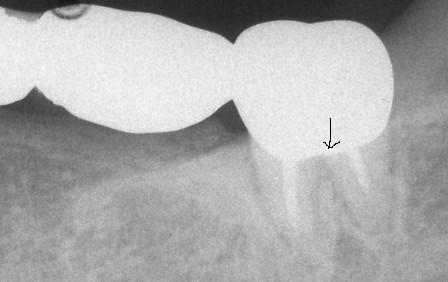

下顎7番の頬側歯茎部カリエスの原因 2025.06.04